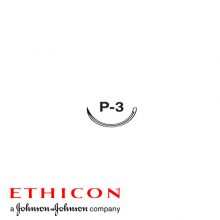

Monosyn® ist ein synthetisches, monofiles, mittelfristig resorbierbares chirurgisches Nahtmaterial aus Glykonat, erhältlich in ungefärbt für den Verschluss oberflächlicher Wunden und in violett für die restlichen Indikationen. Monosyn® bietet exzellente Handhabungseigenschaften und eine hohe Knotensicherheit. Monosyn® wird empfohlen für die Approximation aller Weichteilgewebe.